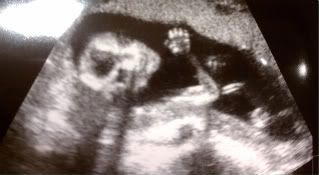

Here is a picture where Chris said he was waving at us:

He still looks like a skeleton at this stage...you can see that he is looking at the camera. And we can see that he at least has all five fingers on the hand he is "waving" with!